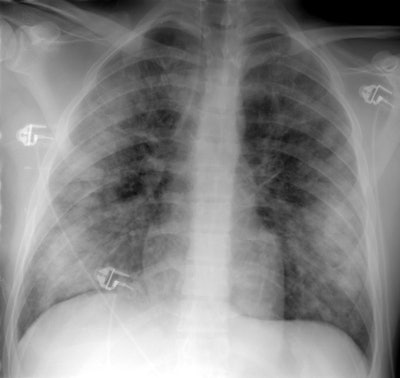

Acute eosinophilic pneumonia:

The patient shown below presented with respiratory distress. The chest radiograph demonstrated bilateral diffuse, but predominantly peripheral areas of airspace consolidation. The bronchoalveolar lavage fluid demonstrated a 37% eosinophil count. The patient demonstrated rapid clinical and radiographic improvement with steroid therapy. (Click on image to enlarge)